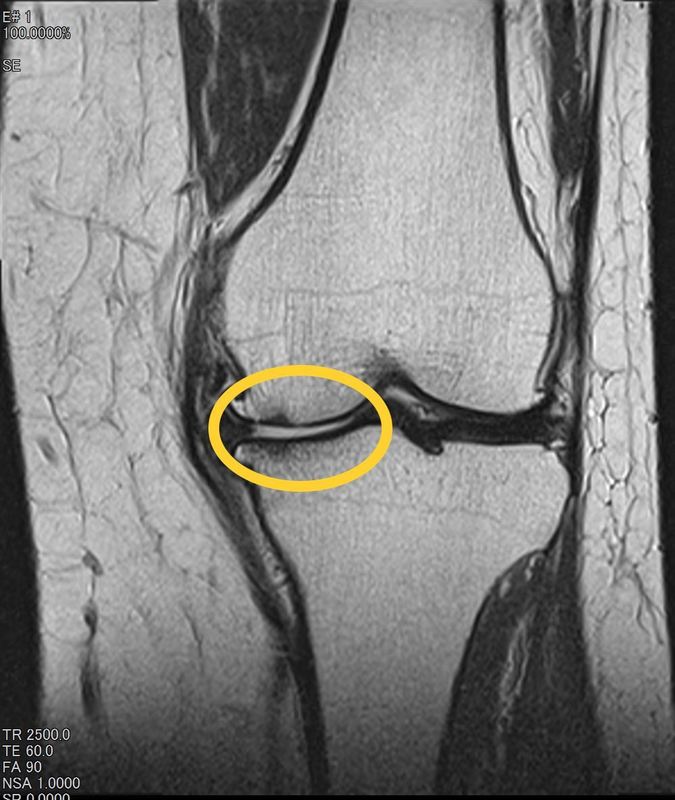

徒手検査や症状からもある程度予測可能です。単純X線写真(レントゲン)では、半月板は写りません。なので検査や症状から半月板損傷が疑わしければMRI検査します。

関節の間が白く映ると(高信号)と半月板が損傷し、炎症を起こしているサインです。